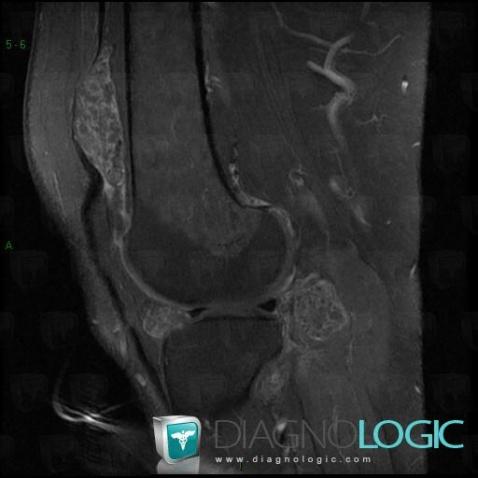

Ostéochondromatose synoviale, Articulations fémoro tibiales / Echancrure, Articulation fémoro patellaire, IRM

- Diagnostic Ostéochondromatose synoviale, Localisation(s) Articulations fémoro tibiales / Echancrure, comportant les gammes Lésions de la graisse de hoffaArticulation fémoro patellaire, comportant les gammes Masse des parties molles juxta articulaires, Arthropathie avec nodules des parties molles, Masse ou épaississement synovial